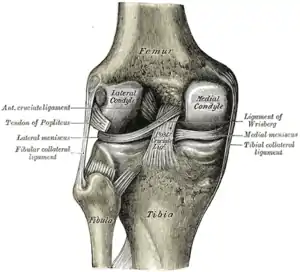

Intracapsular

The knee is stabilized by a pair of cruciate ligaments. These ligaments are both extrasynovial, intracapsular ligaments.[17] The anterior cruciate ligament (ACL) stretches from the lateral condyle of femur to the anterior intercondylar area.[13] The ACL is critically important because it prevents the tibia from being pushed too far anterior relative to the femur.[13] It is often torn during twisting or bending of the knee.[18] The posterior cruciate ligament (PCL) stretches from medial condyle of femur to the posterior intercondylar area. This ligament prevents posterior displacement of the tibia relative to the femur.[13] Injury to this ligament is uncommon but can occur as a direct result of forced trauma to the ligament.

The transverse ligament stretches from the lateral meniscus to the medial meniscus. It passes in front of the menisci. It is divided into several strips in 10% of cases.[10]: 208 The two menisci are attached to each other anteriorly by the ligament.[19] The posterior (of Wrisberg) and anterior meniscofemoral ligaments (of Humphrey) stretch from the posterior horn of the lateral meniscus to the medial femoral condyle. They pass anterior and posterior to the posterior cruciate ligament respectively.[13][10]: 208 The meniscotibial ligaments (or "coronary") stretches from inferior edges of the menisci to the periphery of the tibial plateaus.

Cruciate ligaments

Cruciate ligaments Left knee-joint from behind, showing interior ligaments.